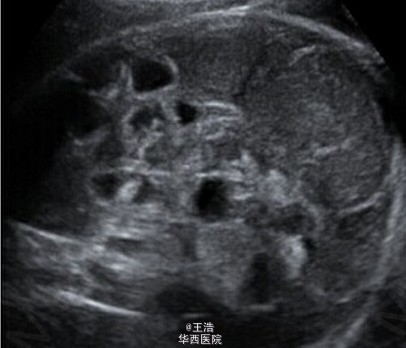

一名 35 岁初产妇,孕龄到达 30 周时出现了宫缩征象,但没有显示胎儿窘迫。超声显示胎儿发育,多普勒指数,羊水均正常。发现强回声的肠管轻度扩张,但不伴有形态学异常。病原体(TORCH)筛查阴性。第二天检查发现肠扩张伴有高回声点推断发生了进展并出现腹水,因此怀疑肠穿孔和胎粪性腹膜炎。 于是对产妇进行了紧急剖腹产。剖出一名男婴,重 2620g,在第 5 分钟及第 10 分钟 Apgar 得分都是 9 分。新生儿呼吸不稳定,腹部重度膨胀水肿呈铁青色,腹膜炎。对新生儿进行了紧急剖腹手术。术中发现证实了接生前的的诊断。切除了 50cm 坏死的回肠,且必要的实施了肠造口术。Takacs ZF, Meier CM, Solomayer EF, Gortner L, Meyberg-Solomayer G. 2014. Prenatal diagnosis and management of an intestinal volvulus with meconium ileus and peritonitis. Arch Gynecol Obstet. 290(2): 385-7.